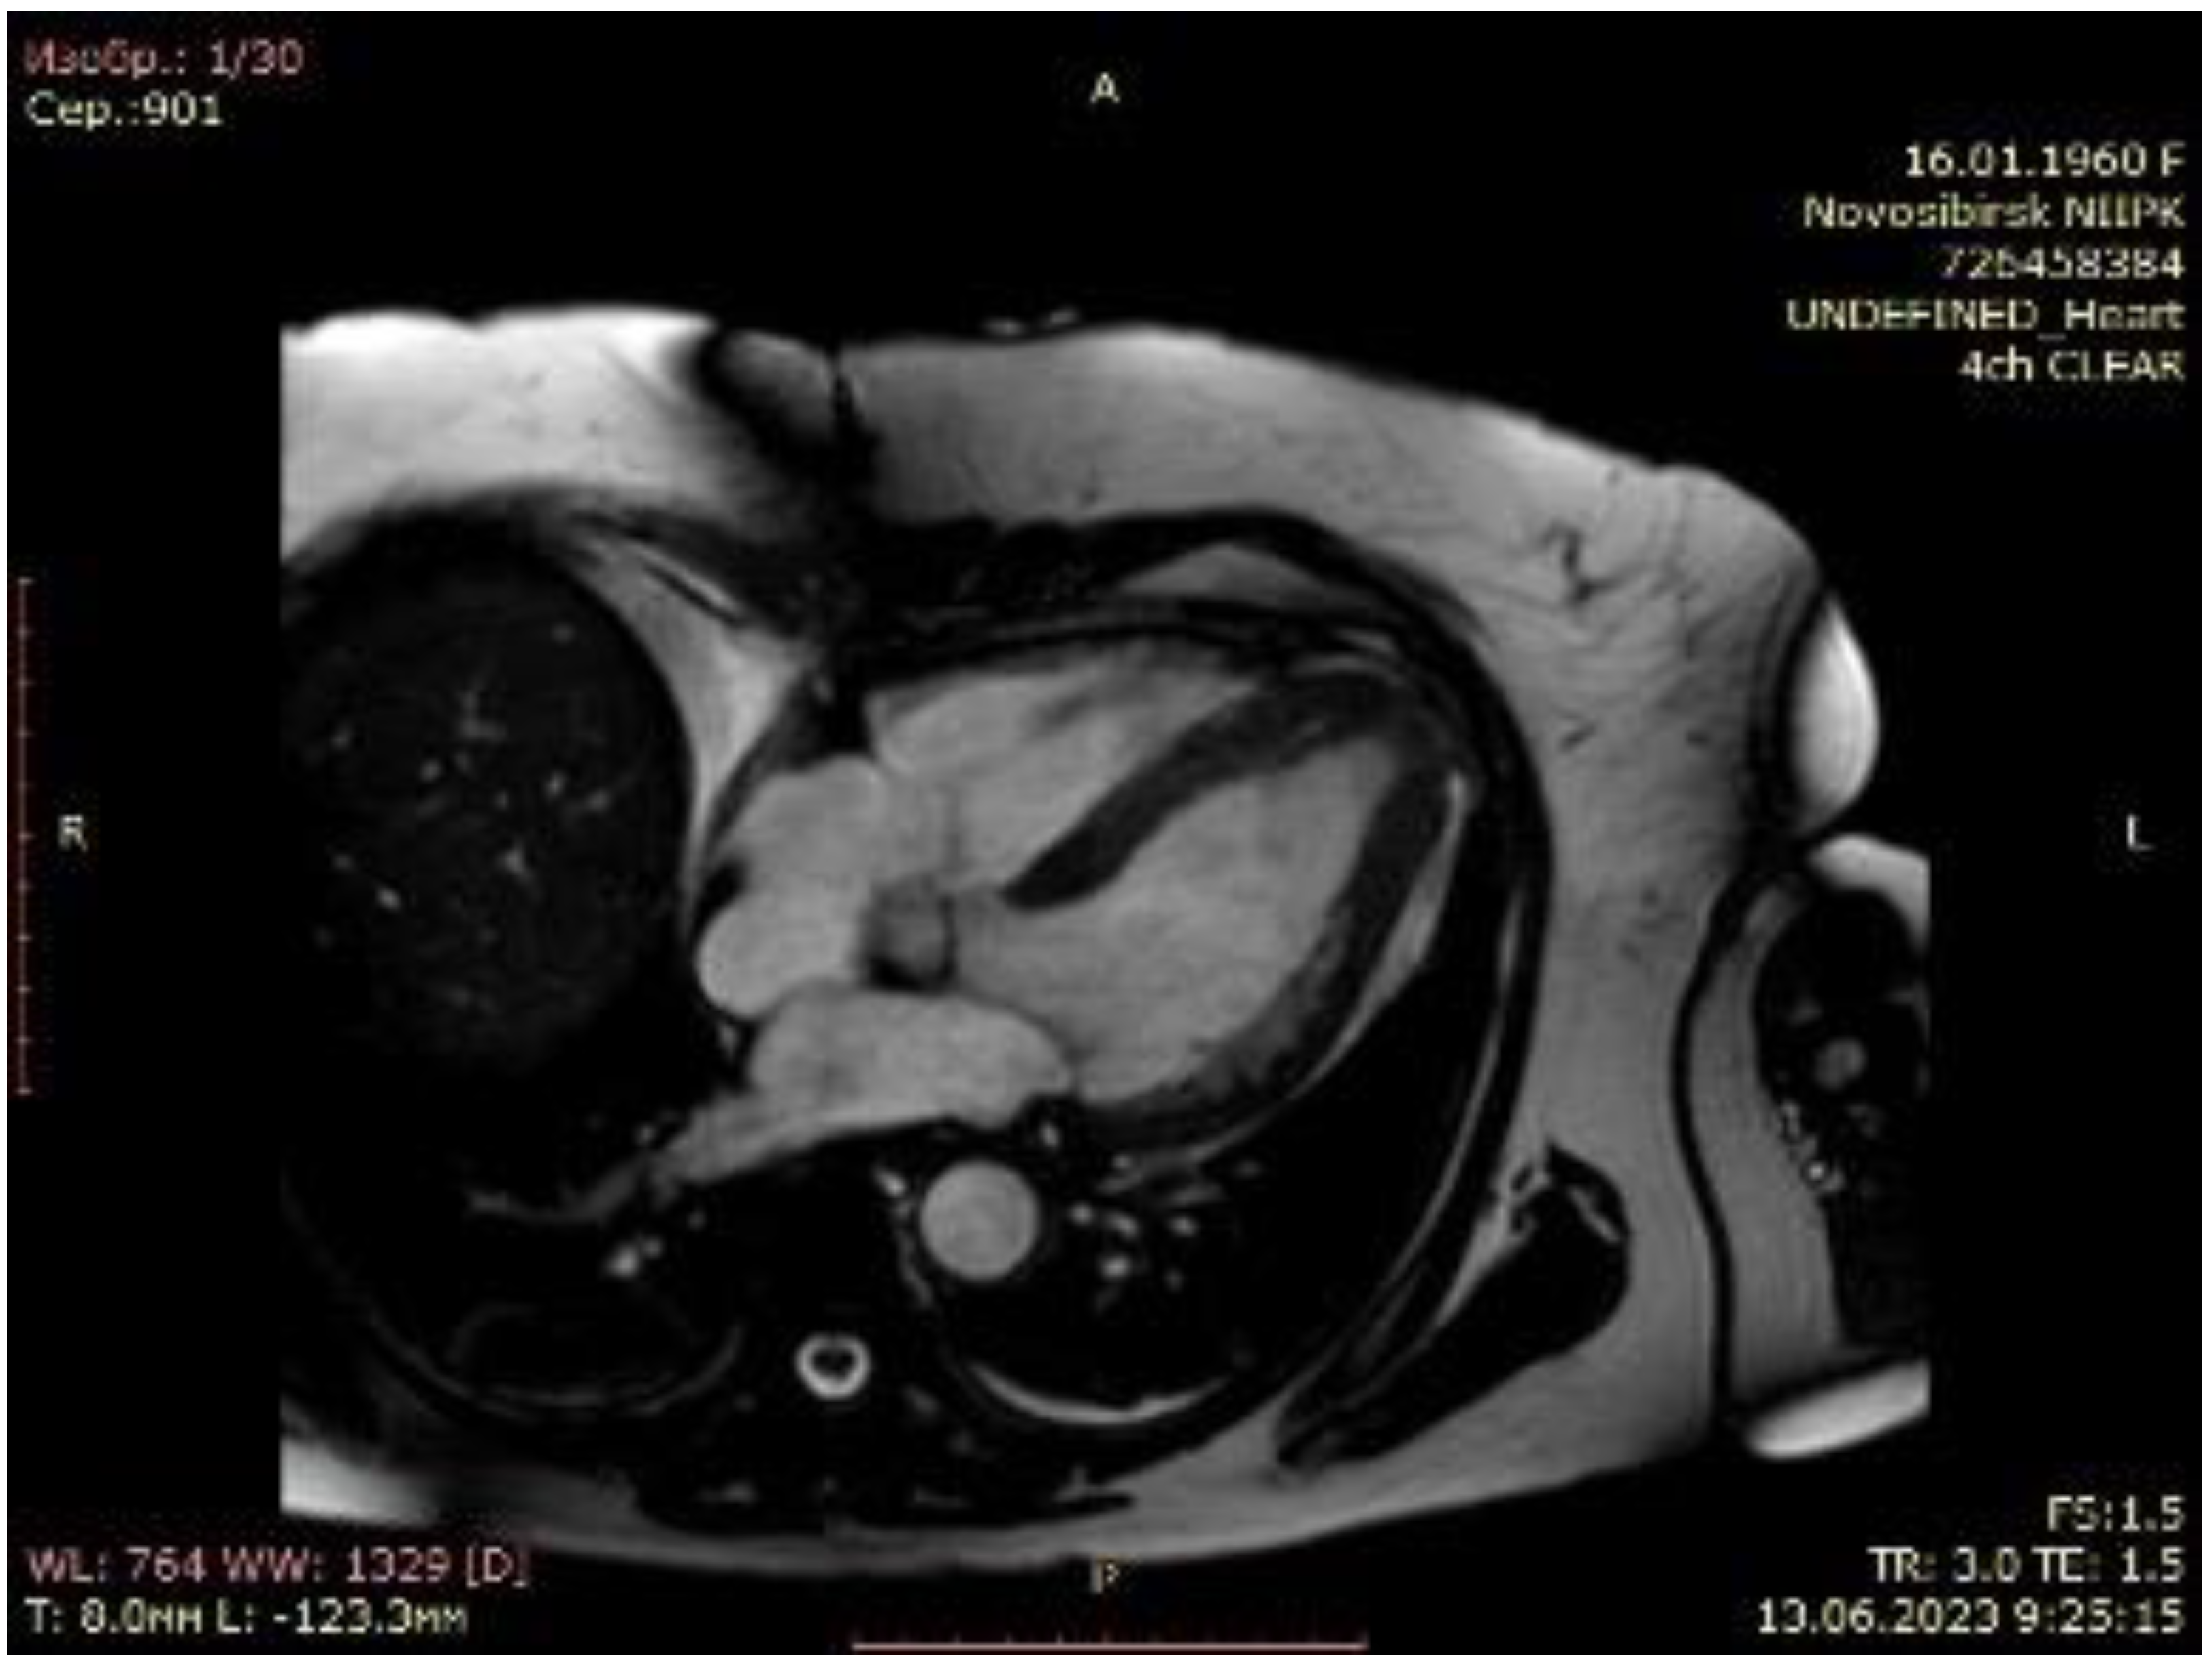

Figure 5.

Cardiac magnetic resonance imaging of patient with apical hypertrophic cardiomyopathy after transapical myectomy.

The post-operative period was unconventional. Post-operative transthoracic echocardiography showed marked LV cavity enlargement compared with the baseline data: LV EDV, 74 mL; LV EF, 65%; and LV SV index increased to 27 mL/m2 (Figure 4, Supplementary Video S4). The maximum LVOT gradient provoked by the exercise was 6 mmHg. A control cardiac MRI underlined the achievement of LV augmentation: LV EDV, 86.9 mL and LV EF, 64%. The maximum septal thicknesses in the basal, midventricular, and apical parts were 11, 10, and 7 mm, respectively; the maximum LV lateral wall thicknesses were 7, 7, and 3 mm, respectively; the maximum LV posterior wall thicknesses were 9, 8, and 9 mm, respectively; and the maximum LV anterior wall thicknesses were 8, 7, and 7 mm, respectively (Figure 5, Supplementary Video S5). The patient was discharged to the rehabilitation facility 7 days after surgery with a stable sinus rhythm. Furthermore, 6 months after the transapical myectomy, the patient was in NYHA Class I, with a 6 min walk test score of 420 m.